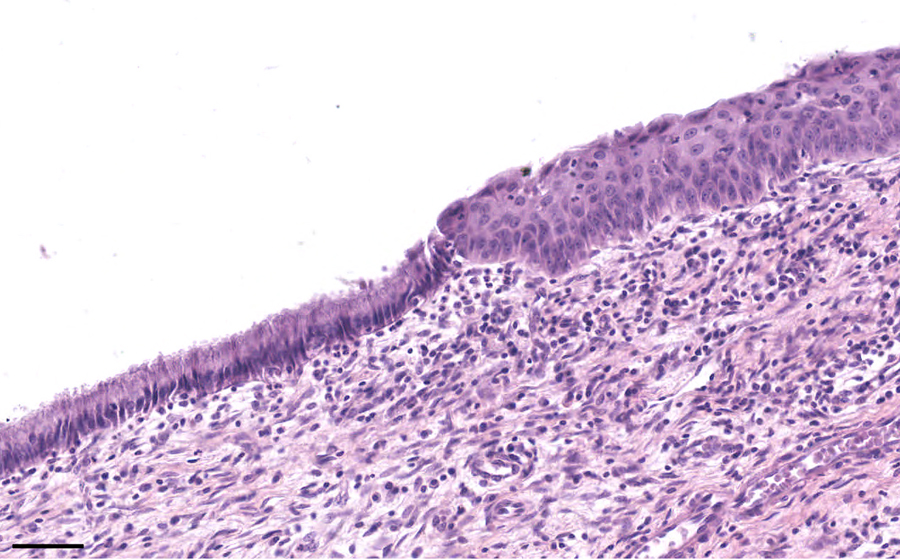

Slide 3: Chronic cervicitis and metaplasia

Histologic section of cervix from a patient with chronic cervicitis (click here to review normal tissue)

Section of normal cervix

Normal image 1 - 50X

Normal Slide - Image 1